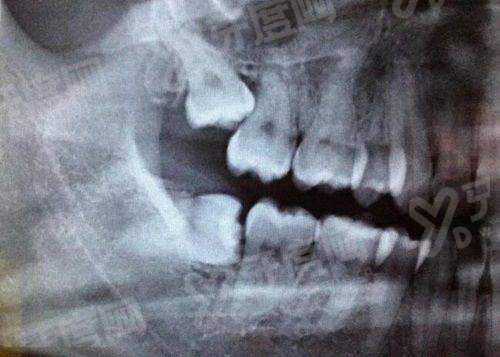

1、医院引进了精良的口腔医疗设备,如数字化口腔CT机、口腔种植机、牙齿美白仪等。这些设备能够为医生提供更清晰、正确的诊断依据,提高治疗的精细度和效率。例如数字化口腔CT机可以360度全方面展示口腔内部结构,帮助医生更好地制定种植和矫正方案。